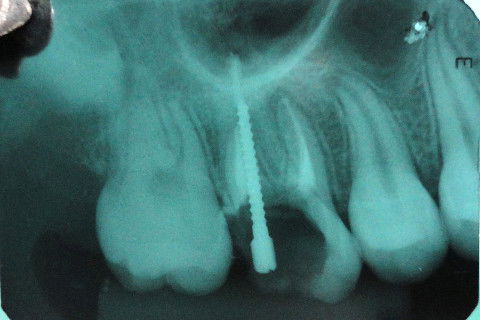

Aspecto Radiográfico após tratamento endodôntico concluído

Cimentação de Pino Metálico Pré- Fabricado